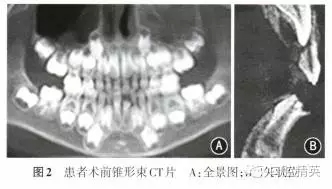

患者男性,7歲10個月,因左下乳前牙脫落后長出一牙尖半年余要求治療,于2014年11月至南昌大學(xué)附屬口腔醫(yī)院口腔頜面外科門診就診。患者既往體健,無牙病及外傷史,無家族史。體格檢查示身體發(fā)育正常,口腔檢查:II缺失,l缺牙區(qū)唇側(cè)可見一圓錐形牙尖突出于牙齦表面,色澤正常(圖1);66616已萌出,混合牙列,余未見明顯異常。錐形束CT檢查示1唇側(cè)鷹爪狀畸形尖,直徑約1.0 mm,長度約3.2 mm,尖端離切緣約2.6 mm,不與髓腔相通;切緣形態(tài)亦發(fā)育異常,近髓角;牙根發(fā)育至根長1/2左右,根尖呈喇叭狀;無先天性牙缺失及額外牙(圖2)。

診斷:1畸形唇側(cè)尖并遲萌。處理:考慮到牙根剛發(fā)育至根長1/2左右,在保留患牙、保存活髓的原則下,經(jīng)患者家屬知情同意,于局麻下行“1開窗助萌術(shù)+畸形唇側(cè)尖端部分調(diào)磨術(shù)+切緣及尖端75%氟化鈉甘油糊劑局部涂布”,術(shù)中見1畸形唇側(cè)尖明顯,尖頂幾乎與切緣平齊(圖3)。